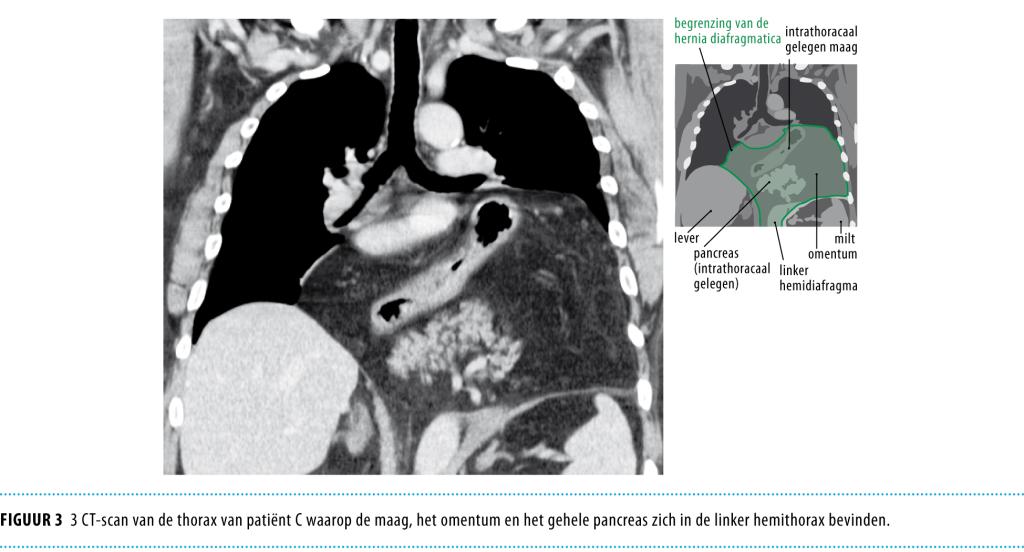

Een ‘sliding’ hiatushernia is de meest voorkomende hernia diafragmatica. Hierbij is de gastro-oesofageale overgang door de hiatus oesophageus naar het mediastinum posterius gehernieerd. Dit type hernia kan refluxklachten veroorzaken, zoals retrosternaal zuurbranden en regurgitatie. Het is frequent aanwezig bij patiënten met gastro-oesofageale refluxziekte.1 Een zeldzamer type hernia is de para-oesofageale hiatushernia waarbij de fundus van de maag langs de slokdarm naar de thorax is gehernieerd.2 Deze hernia’s kunnen klachten veroorzaken die berusten op obstructie van de voedselpassage en beklemming van de breukinhoud met dilatatie of circulatiestoornissen van de gehernieerde maag. Deze klachten zijn meestal aspecifiek en kunnen bestaan uit intermitterende epigastrische of substernale pijnklachten, snel een vol gevoel tijdens de maaltijd, dysfagie en misselijkheid en braken. Het natuurlijk beloop van een para-oesofageale hernia is progressief waarbij uiteindelijk de gehele maag in de thorax terecht kan komen. Daarbij kunnen ook andere organen, zoals het omentum, het…